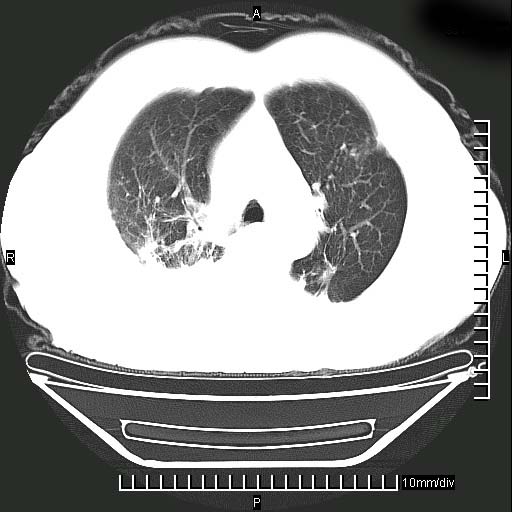

既往肺结核,近10几天,咳嗽,咳痰,右侧胸痛,疼痛较明显,右上肺斑块考虑结核灶胸膜粘连,增强,可惜动脉期没有定好,未见强化,可延迟4分后又见较明显强化,中心见低密度影,如果说结核是边缘强化,可这个灶强化的面积挺大的,让人很挠头。

1)两肺继发性肺结核。2)右侧胸膜增厚+少量胸腔积液。